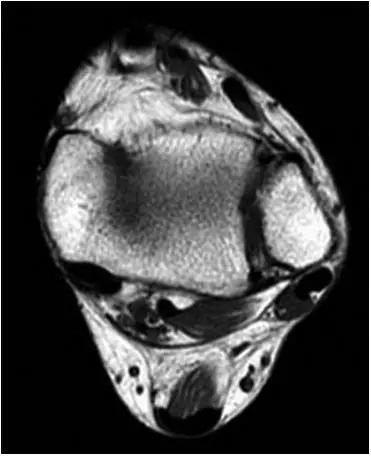

①踝关节外侧沟内异常软组织

轴位示意图示后内侧撞击综合征:M:内踝;L:外踝;TP:胫后肌腱;FDL:趾长屈肌腱;Talus:距骨。短箭:距骨胫骨间肌腱深层纤维;箭头:距骨胫骨间肌腱后部纤维。